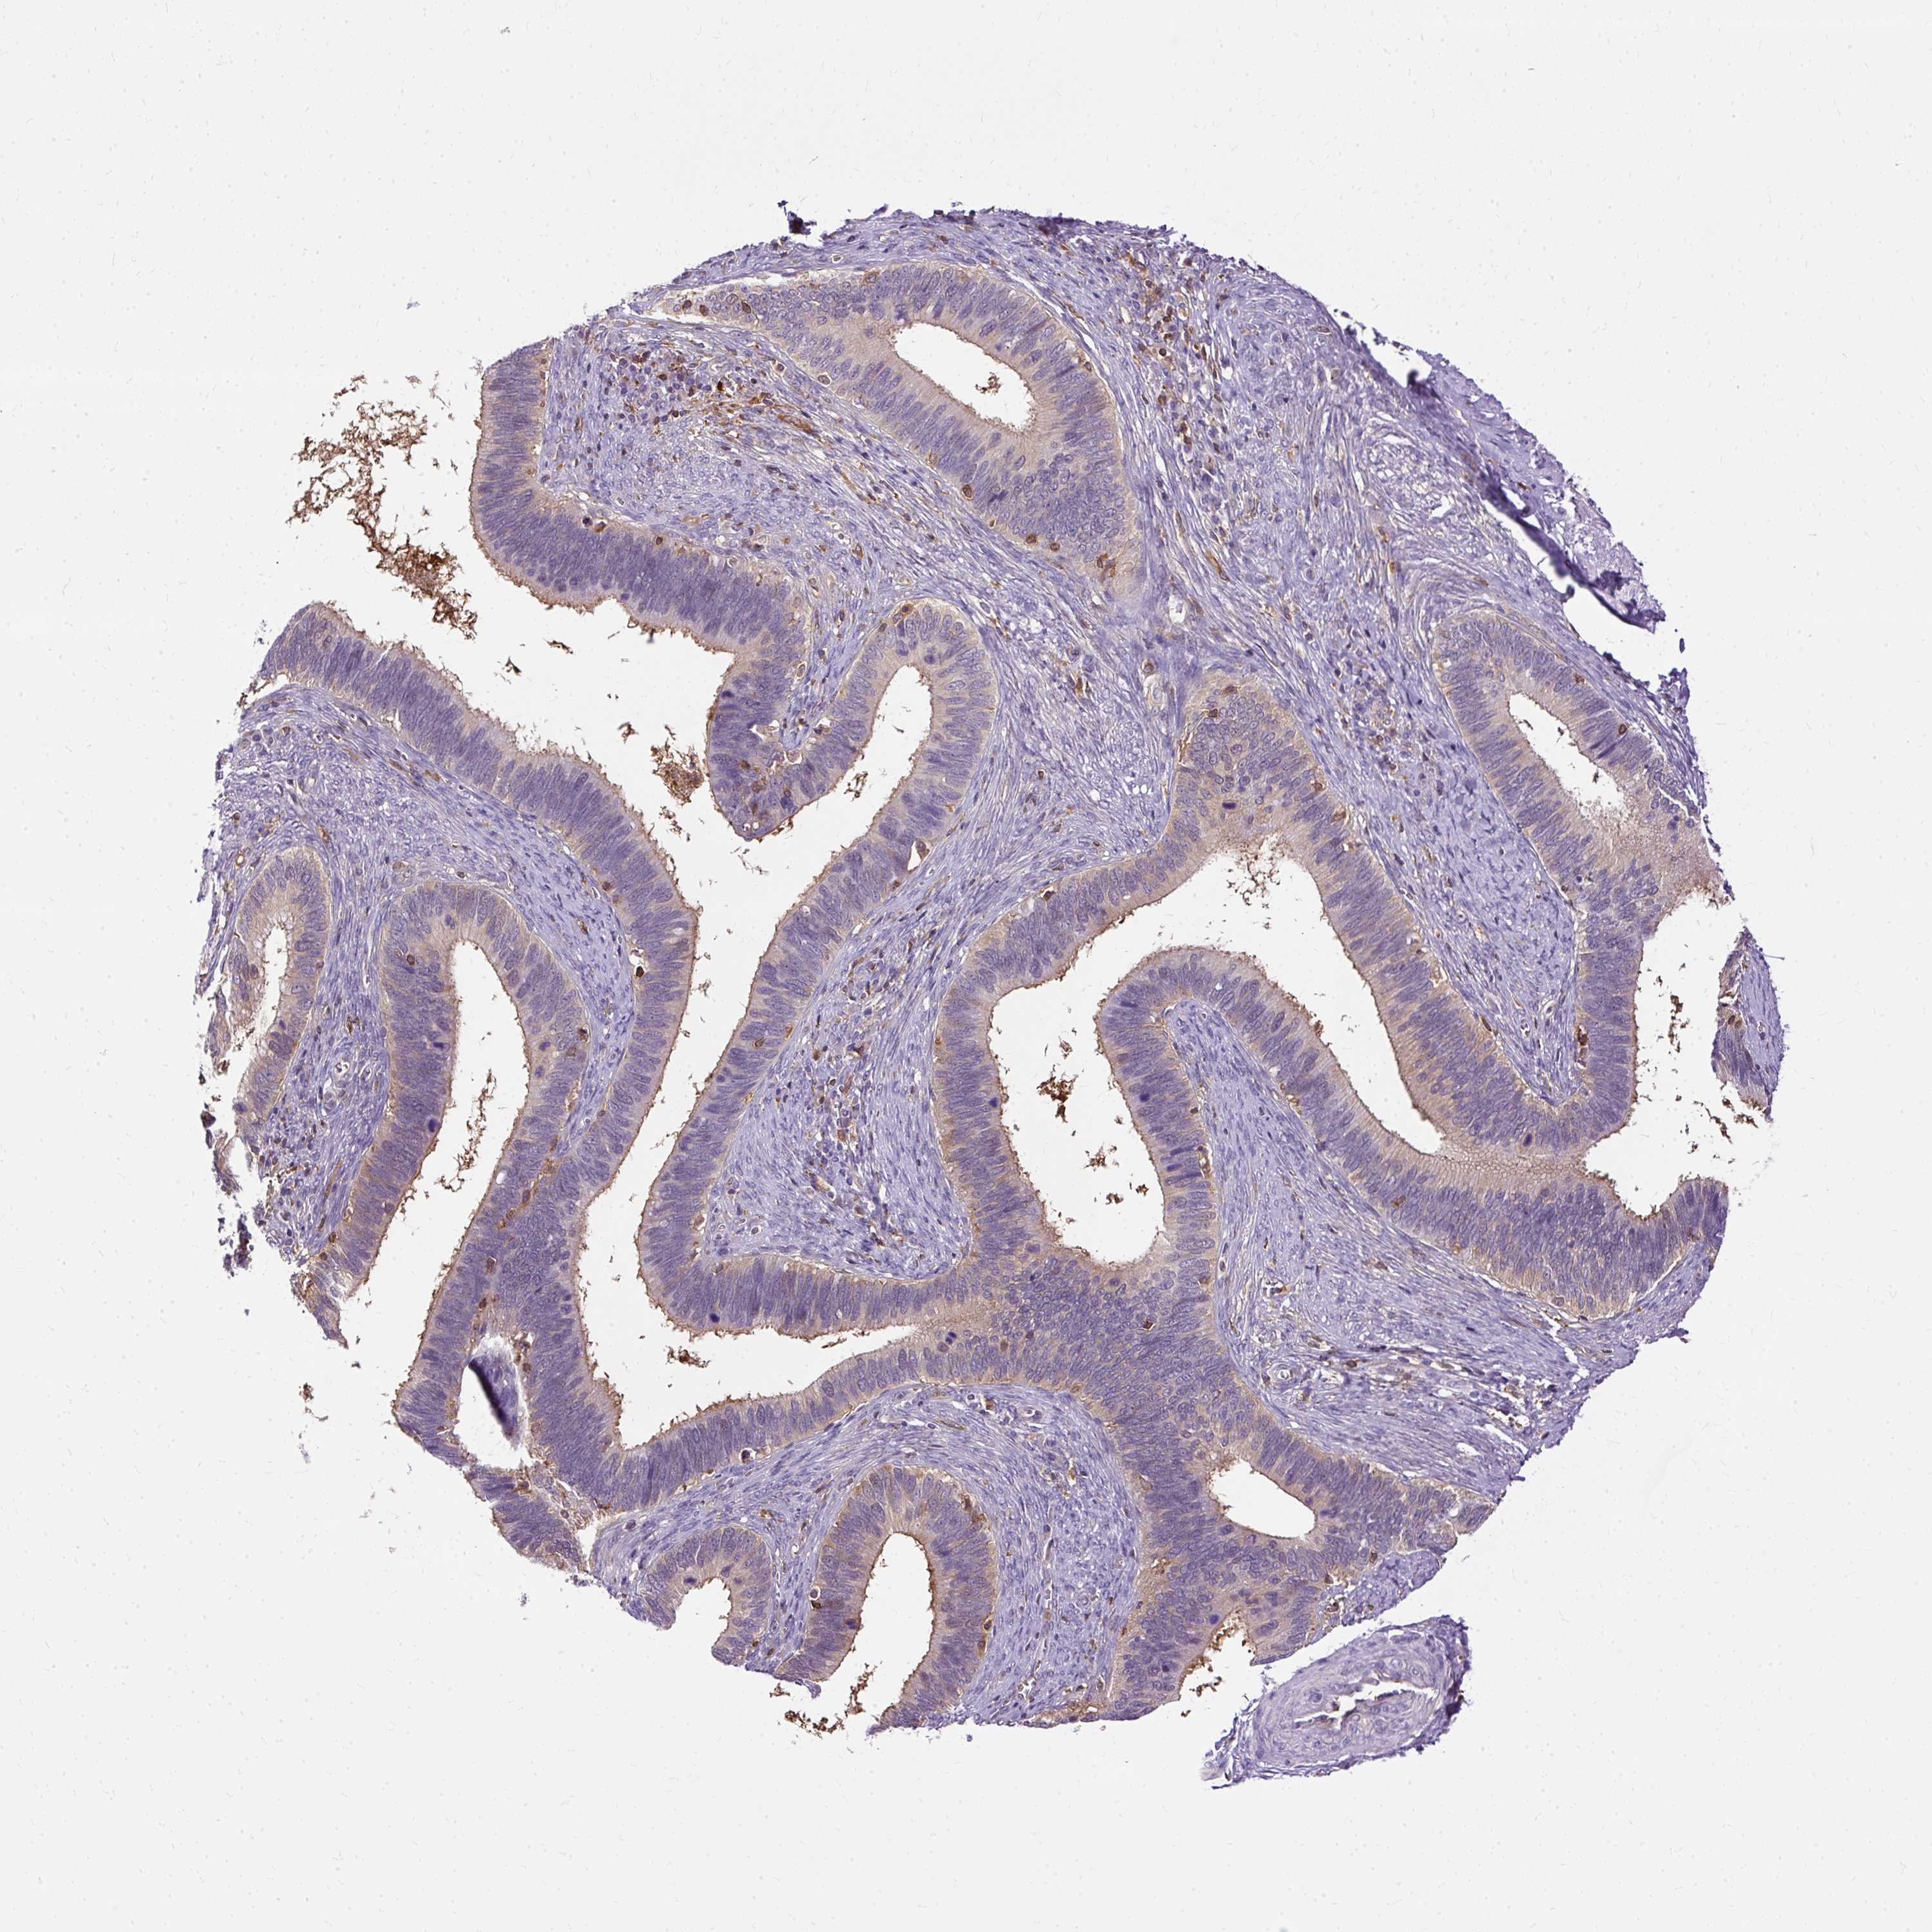

CERVICAL CANCER - Protein expressioni

A mouse-over function shows sample information and annotation data. Click on an image to view it in a full screen mode. Samples can be filtered based on level of antibody staining by selecting one or several of the following categories: high, medium, low and not detected. The assay and annotation is described here.

Note that samples used for immunohistochemistry by the Human Protein Atlas do not correspond to samples in the TCGA dataset.

Antibody stainingi

Antibody staining in the annotated cell types in the current human tissue is reported as not detected, low, medium, or high, based on conventional immunohistochemistry profiling in selected tissues. This score is based on the combination of the staining intensity and fraction of stained cells.

Each image is clickable and will lead to virtual microscopy that enables deeper exploration of all samples and also displays staining intensity scores, fraction scores and subcellular localization as well as patient and tissue information for each sample.

Antibody HPA053874

Staining

High

Medium

Low

Not detected

Intensity

Strong

Moderate

Weak

Negative

Quantity

>75%

75%-25%

<25%

None

Location

Nuclear

Cytoplasmic/membranous

Cytoplasmic/membranous,nuclear

Adenocarcinoma, NOS